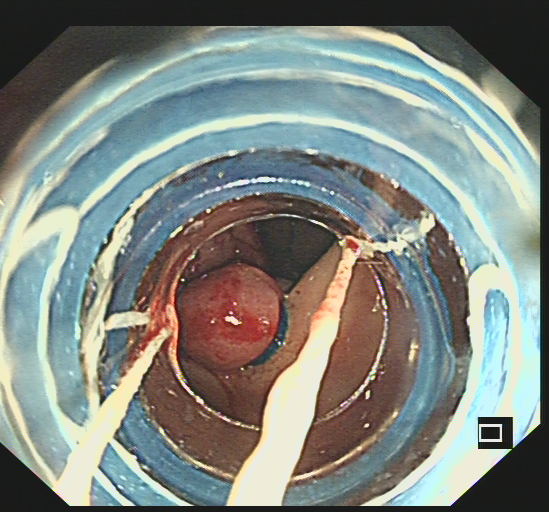

内痔套扎前

内痔套扎后

杨丽博士为患者行肠镜下套扎术

数天前,家住益阳安化33岁的王先生因头晕乏力就诊于当地神经内科,在经过常规体检后发现,患者有严重贫血,考虑为消化道疾病,经推荐转入湖南省人民医院消化内科就诊。入院后检查血红蛋白38g/L,属于重度贫血。为尽快明确出血点,经消化内科团队综合评估后对患者行急诊胃肠镜检查,最终发现导致消化道大出血的病因是内痔出血,并在内镜下精准地找到了内痔的出血破口。当即,科室管床医生与患者沟通并取得同意后,消化内科杨丽博士为患者实施了内镜下内痔套扎术”。整个手术过程患者一直清醒,手术全程仅用时15分钟。“整个手术过程像做梦一样,醒来就不便血了,痔疮也好了”王先生高兴的说道。术后复查血红蛋白回升至60g/L,术后第二天出院。

杨丽博士介绍,近年来随着内镜技术的广泛应用,痔疮的内镜治疗也在临床广泛开展,内镜下内痔套扎和硬化治疗是一种简单易行、疗效确切的内镜治痔新方法。2021年中国内镜专家组制定了《中国消化内镜内痔真理指南及共识》,针对I—III度内痔,可以采取内镜下内痔套扎术或硬化治疗,尤其对有脱垂的内痔患者,套扎治疗效果更佳。内痔套扎术可即刻将脱出的痔向上牵拉,随后套扎的粘膜缺血坏死并脱落,局部组织瘢痕化可形成持久牵拉作用。套扎的部位可以是痔核,也可以是痔上的直肠粘膜,改善患者内痔脱出症状。内镜下内痔套扎术具有痛苦小、花费少、恢复快、疗效佳等特点,可以说是内痔患者的福音。